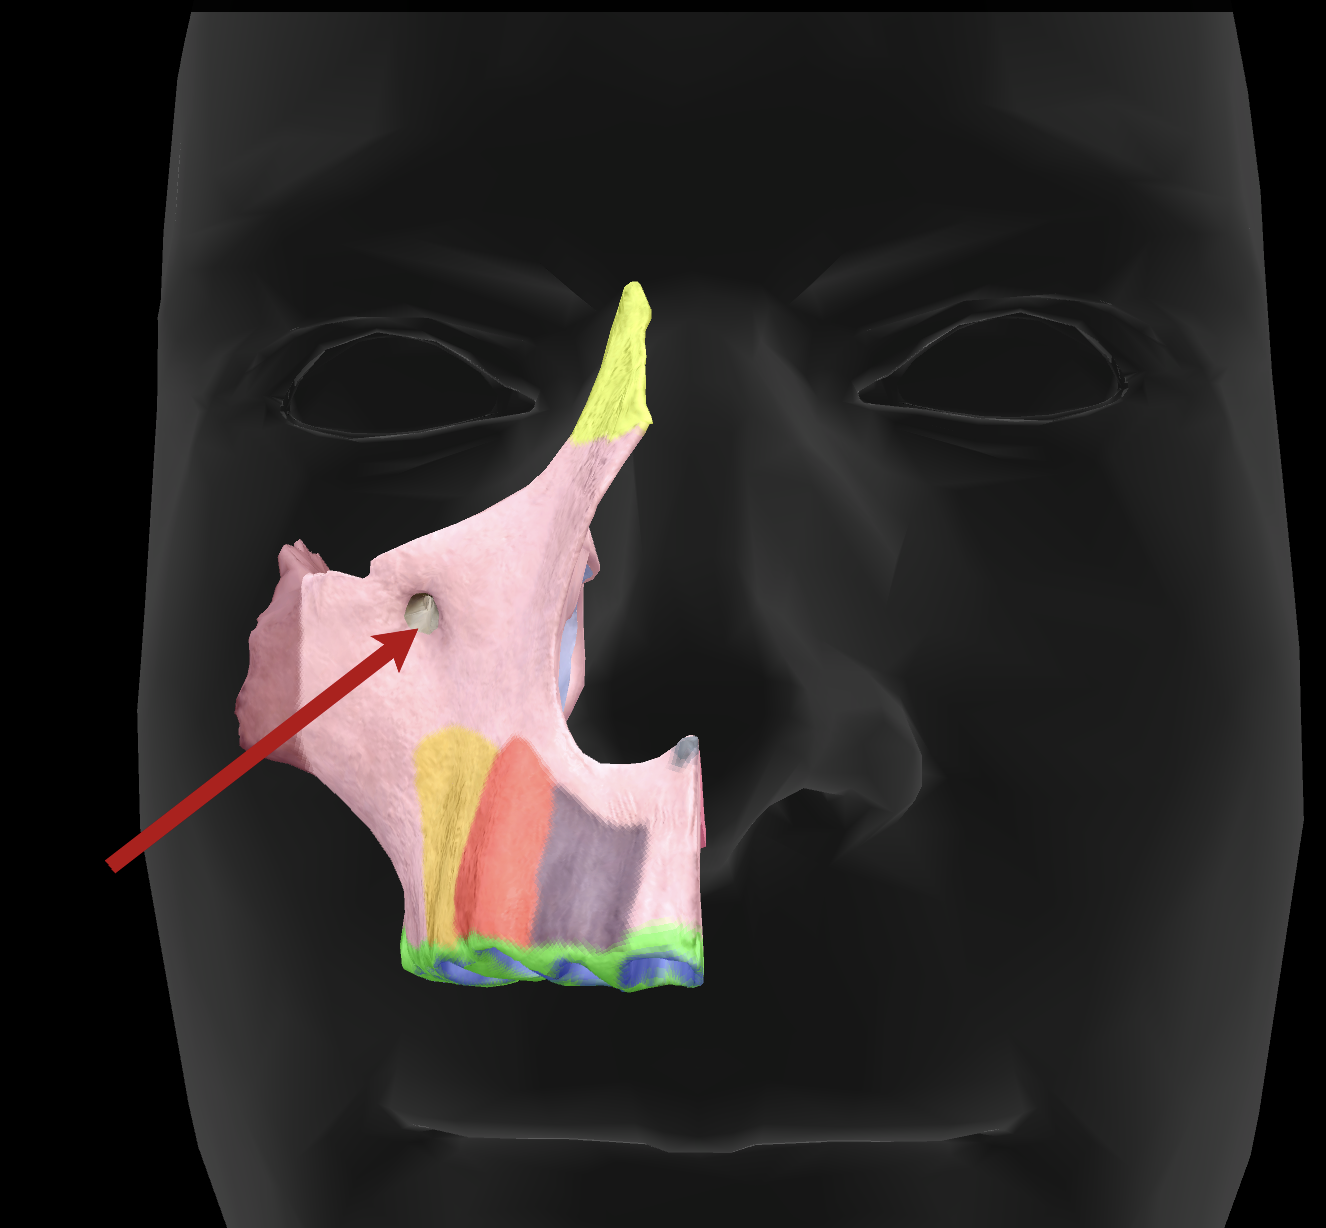

What is the name of this feature?

infraorbital foramen